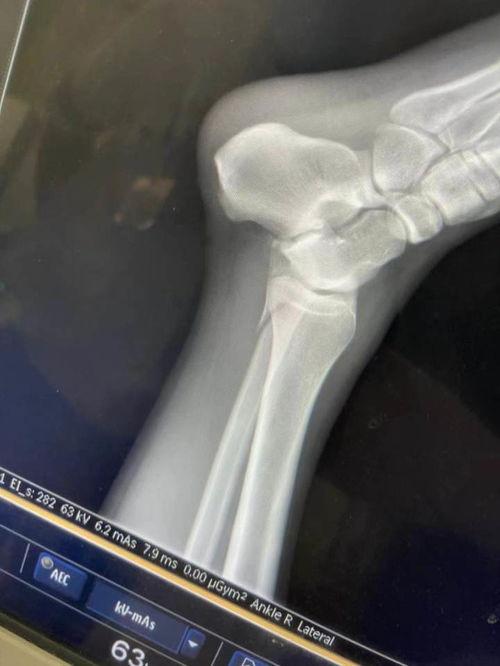

这位网红名叫小美,是抖音上的一位健身达人。那天,她正在拍摄一组瑜伽动作的视频,没想到就在一个难度较高的动作中,脚掌不幸骨折了。这一幕被镜头捕捉下来,瞬间引发了网友们的热议。

小美的脚掌骨折视频一经发布,立刻吸引了大量网友的关注。视频中,小美痛苦的表情、扭曲的身体,还有那让人心疼的呻吟声,都让人感受到了她的痛苦。就是这样一段看似痛苦的画面,却让网友们纷纷点赞,称小美为“坚强女神”。